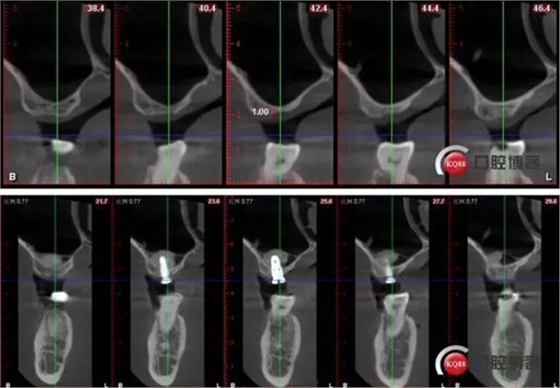

術(shù)后CBCT

術(shù)前術(shù)后CBCT對比: